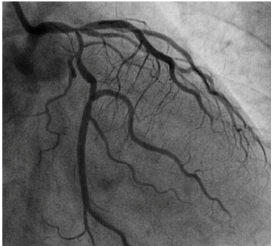

Homem de 47 anos, previamente assintomático, vem à emergência com história de dor precordial há cerca de uma semana com piora progressiva.

Hipertenso, com história familiar para DAC. Colesterol total: 280mg/dl. Realizou cineangiocoronariografia com a imagem apresentada na figura 1.

Figura 1

Fonte: Korean Circ J. 2013 Nov;43(11):761-765. English.

A melhor conduta terapêutica, nesse caso, considerando o conjunto ausência de sintomas e melhora de sobrevida, é